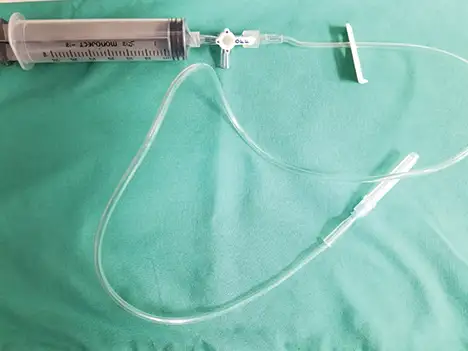

Cystocentesis may also be used therapeutically in patients that have urinary obstruction secondary to uroliths, urethral plugs, and/or neoplasia. Decompressive cystocentesis can alleviate patient discomfort prior to urinary obstruction removal and can lower intraluminal bladder pressure and facilitate retropulsion of urethral plugs/uroliths, potentially easing catheterization.7 Decompressive cystocentesis should be performed with an extension set and a 3-way stopcock to allow for a single needle insertion as opposed to multiple needle insertions. Although decompressive cystocentesis has previously been discouraged, studies have suggested there is minimal risk for bladder rupture/uroperitoneum.8

Additional supplies if removing a large volume of urine

Extension set

Alternatively, a butterfly catheter can be used in smaller patients in lieu of an extension set and needle

3-way stopcock

Larger syringe (12-60 mL)